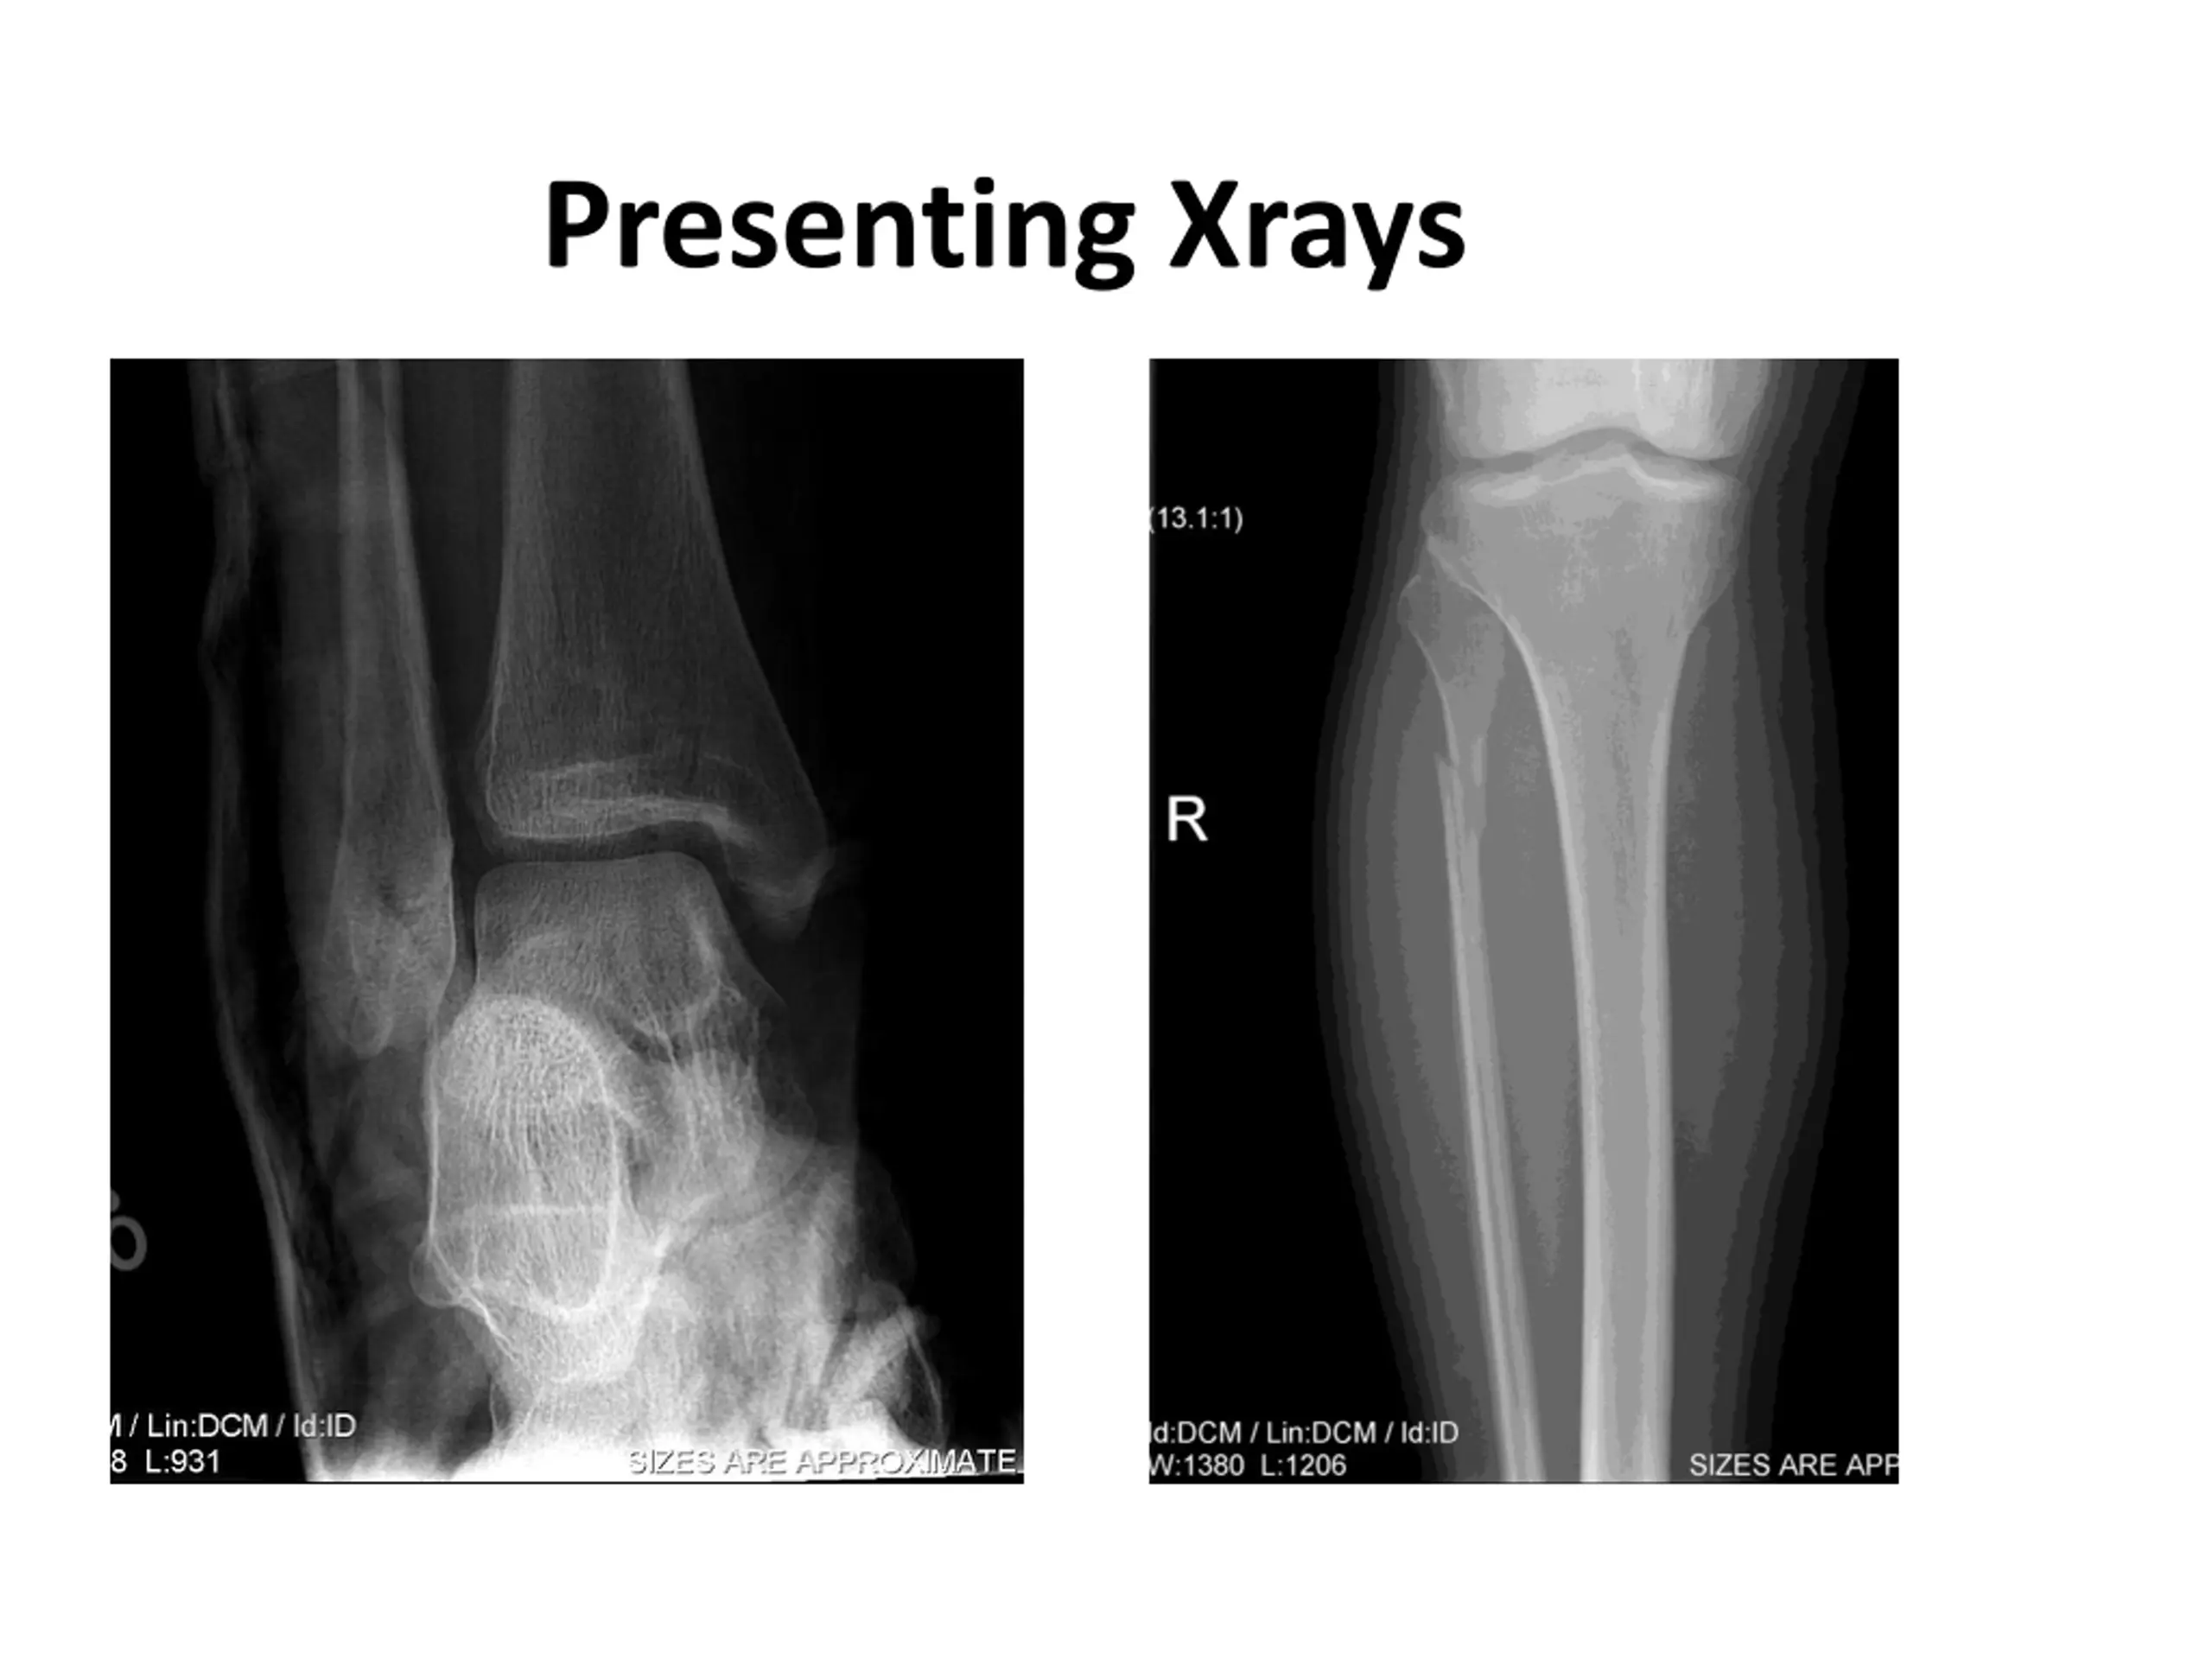

Case 39 YO active female External rotation injury to right lower extremity Fall with leg caught under her Unable to weight bear post injury On exam: Pain at syndesmosis. +ve squeeze test, +ve external rotation test